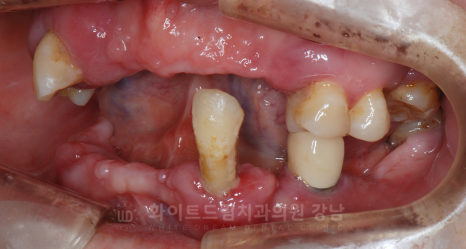

강남역 임플란트 치과, 화이트드림치과 강남 전체 임플란트 사례 (진료 전)

X-RAY 사진을 보면 대부분의 치아가 빠진 상태이고,

그나마 남아있는 치아들도 잇몸뼈에 겨우 매달려 있어 굉장히 심하게 흔들리고 있는 상태였습니다.

심한 치주염으로 인해 대부분의 치아가 빠진 것인데요.

상/하악의 맞닿는 치아가 한 부분밖에 없어 이 부분으로 조금씩 식사하며 지내셨다고 합니다.